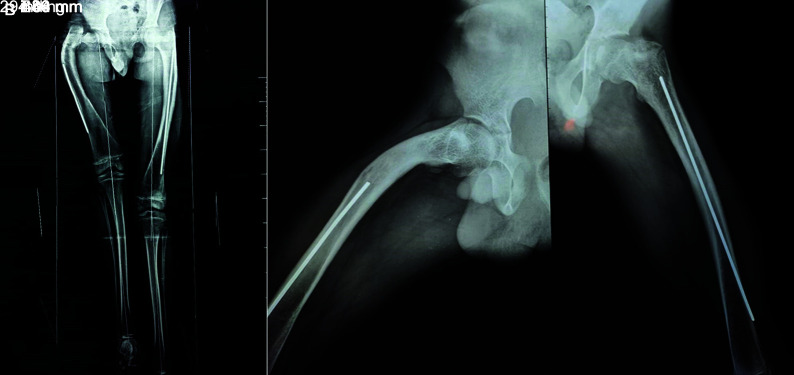

Osteogenesis imperfecta (OI) patients usually sustain repeated fractures from trivial trauma and also have skeletal deformities that affect walking. The bone fragility and repeated fractures produce deformities of the long bones especially in femur and tibia. However, neck of femur (NOF) fractures in OI are rarely described. A 11-year-old male patient known to have OI (Sillence type IV) sustained a NOF fracture after a fall. He also had proximal femoral anterolateral bowing proximally and over an intramedullary (IM) rod inserted 4 years back. He was treated by corrective osteotomy and stabilisation with an IM telescoping nail for the deformed femur and the Wagner technique for the NOF fracture. One year after operation, the patient had recovered satisfactory functional outcome with union of the NOF fracture and correction of the femoral deformity.

Conclusion: The method of the Wagner technique can achieve stable fixation for femoral neck fractures and introduces the least interference with concurrent telescoping nail insertion.